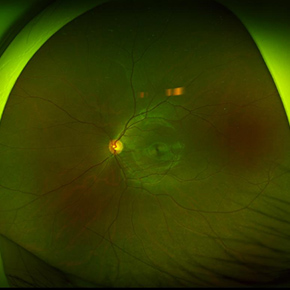

眼底写真検査

網膜の中心部(黄斑・視神経付近)の写真を撮影し、網膜疾患や血管異常の有無を確認

広角眼底写真撮影(最周辺部)

網膜の周辺部まで広範囲を撮影し、網膜裂孔や変性などの異常を中心部以外も含めて早期発見

自発蛍光眼底写真

網膜に含まれる自発蛍光物質を撮影し、加齢黄斑変性・網膜萎縮など、網膜組織の機能異常や変化を評価

眼底光干渉断層系(後眼部OCT)

黄斑部や視神経周辺の断層画像を取得し、網膜の構造変化(黄斑変性・緑内障など)を早期発見

散瞳での眼底観察

瞳孔(黒目)を広げて網膜全体を医師が直接観察し、網膜裂孔・変性・出血などの異常をさらに詳しくチェック